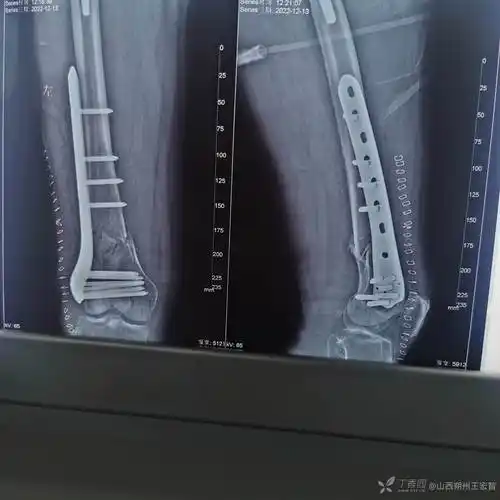

股骨髁间骨折钢板固定